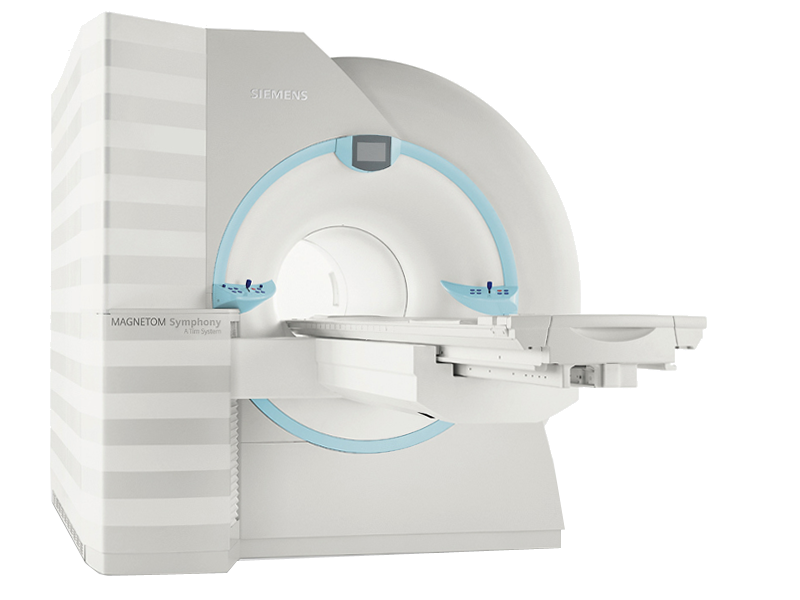

С помощью МРТ врачи диагностируют сложные заболевания. Выявление патологии на начальном этапе заболевания облегчает диагностику и дальнейшее лечение.

С помощью МРТ врачи диагностируют сложные заболевания. Выявление патологии на начальном этапе заболевания облегчает диагностику и дальнейшее лечение.